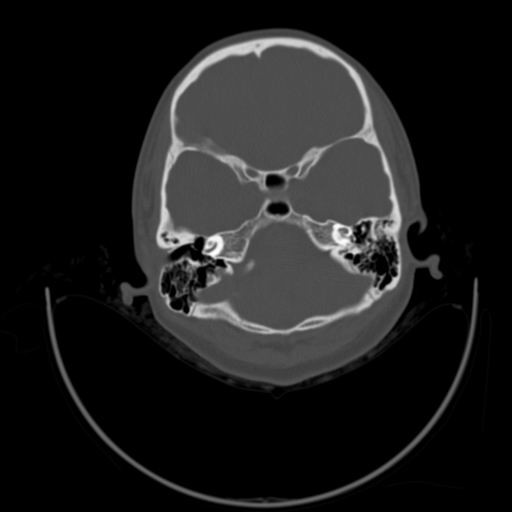

以下是引用随光逐影在2009-3-14 7:58:00的发言:[br]双耳——颞骨ct轴位平扫未见明确异常。